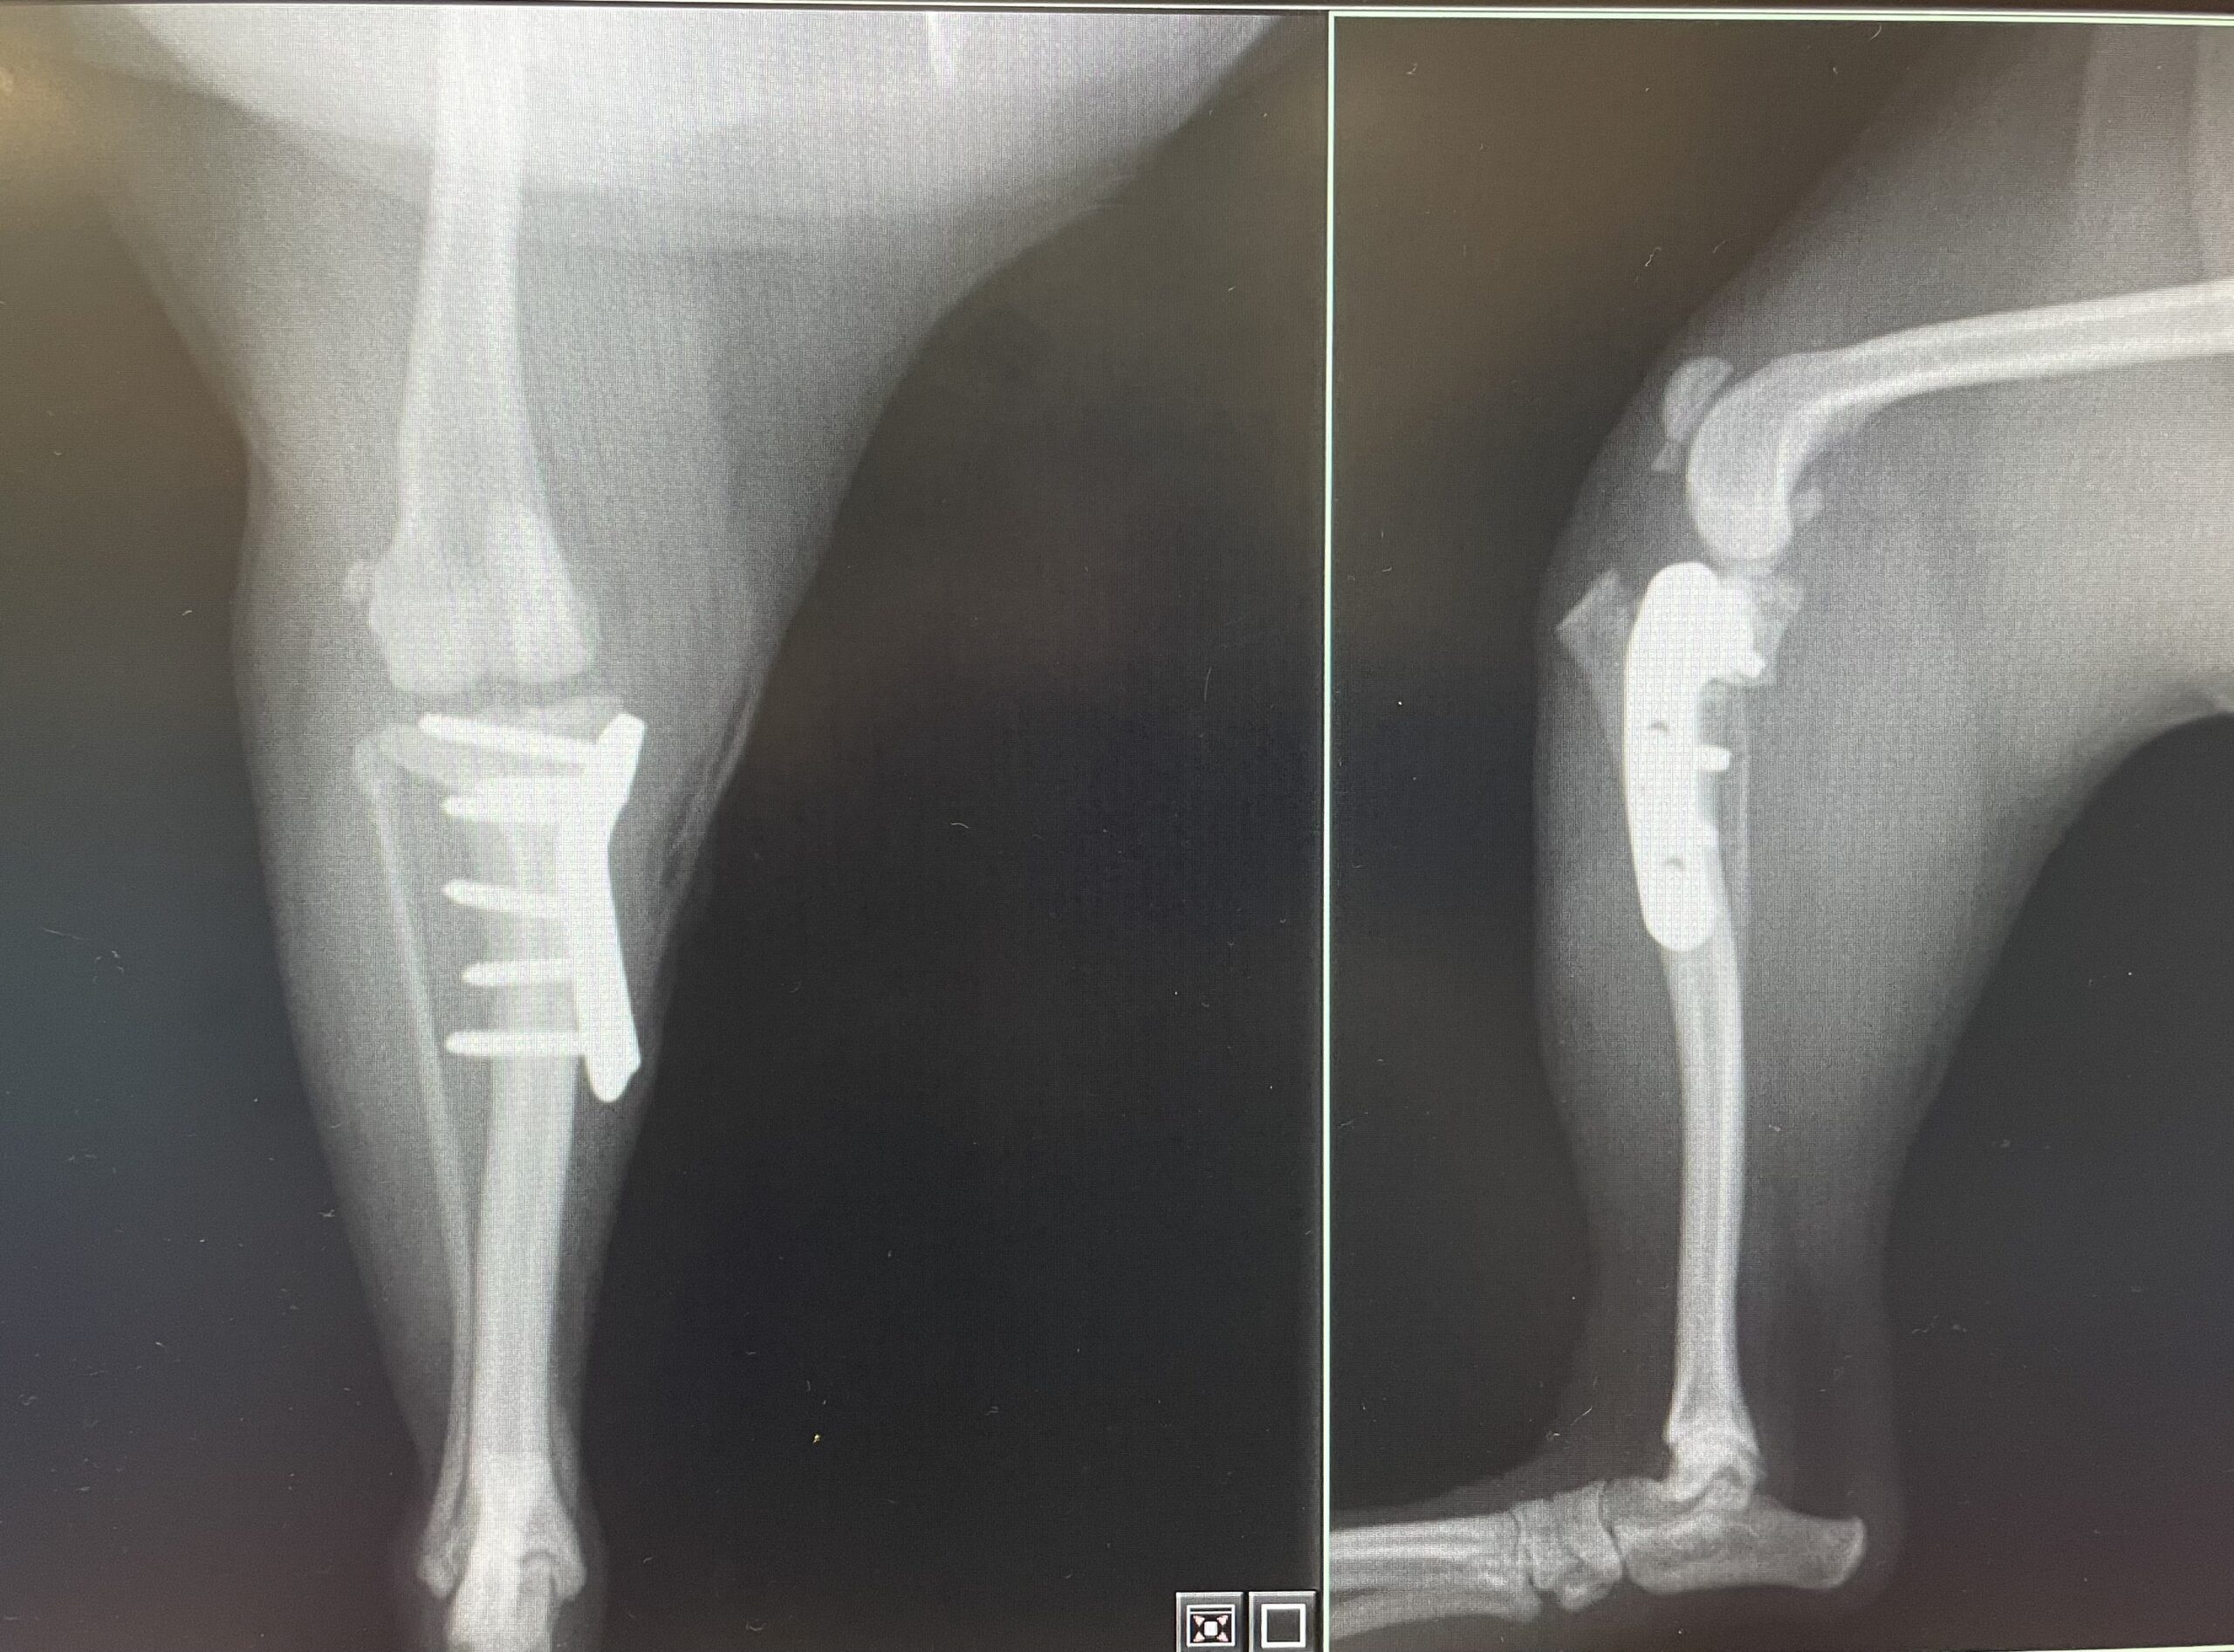

この手術では、脛骨(すねの骨)を円形に骨切りし、骨の角度を変えてプレートで固定するという方法を取ります。

その後、レントゲン検査で骨の治癒を確認しながら、徐々に運動量を増やしていきます。